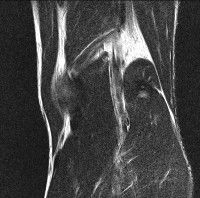

무릎 mri 간단히 봐주실 수 있으시나요 ㅠㅠ

안녕하세요 8년전 십자인대 수술하고 최근 무리한 운동에 무릎 불편감이 생겨서

mri 찍었습니다.

진단결과는 첫 찍은 병원에서 활액막염 이라는 진단을 받았습니다. 혹시 봐주실 수 있으실까요?

올라온 MRI가 단편적이라서 정확한 진단에 어려움이 있지만 십자인대에는 큰 이상이 있지는 않은것 같으며, 무릎관절내 물이 있는 것으로 보아 활액막염의 진단이 맞을 것 같습니다.

하지만 단편적인 영상이기 때문에 촬영병원에서 정확한 판독지 등을 받으시는 것이 좋겠습니다.